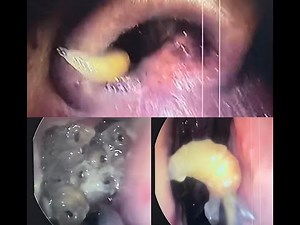

Maggots in Nose/ Nasal Myiasis- Dr. V. Narendrakumar

Nasal myiasis is an opportunistic parasitic infestation of human as well as animals. Infestation of the nasal cavity by dipterous larvae is called nasal myiasis which is commonly seen in developing countries where health and sanitation are poor

MAGGOTS inside the NOSE || Maggots crawling in the nose || Dr. Sharad ENT videos

Nasal Myiasis Maggots of nose

Nasal Myiasis Removal

NASAL MYIASIS, maggots in nose with important stuff